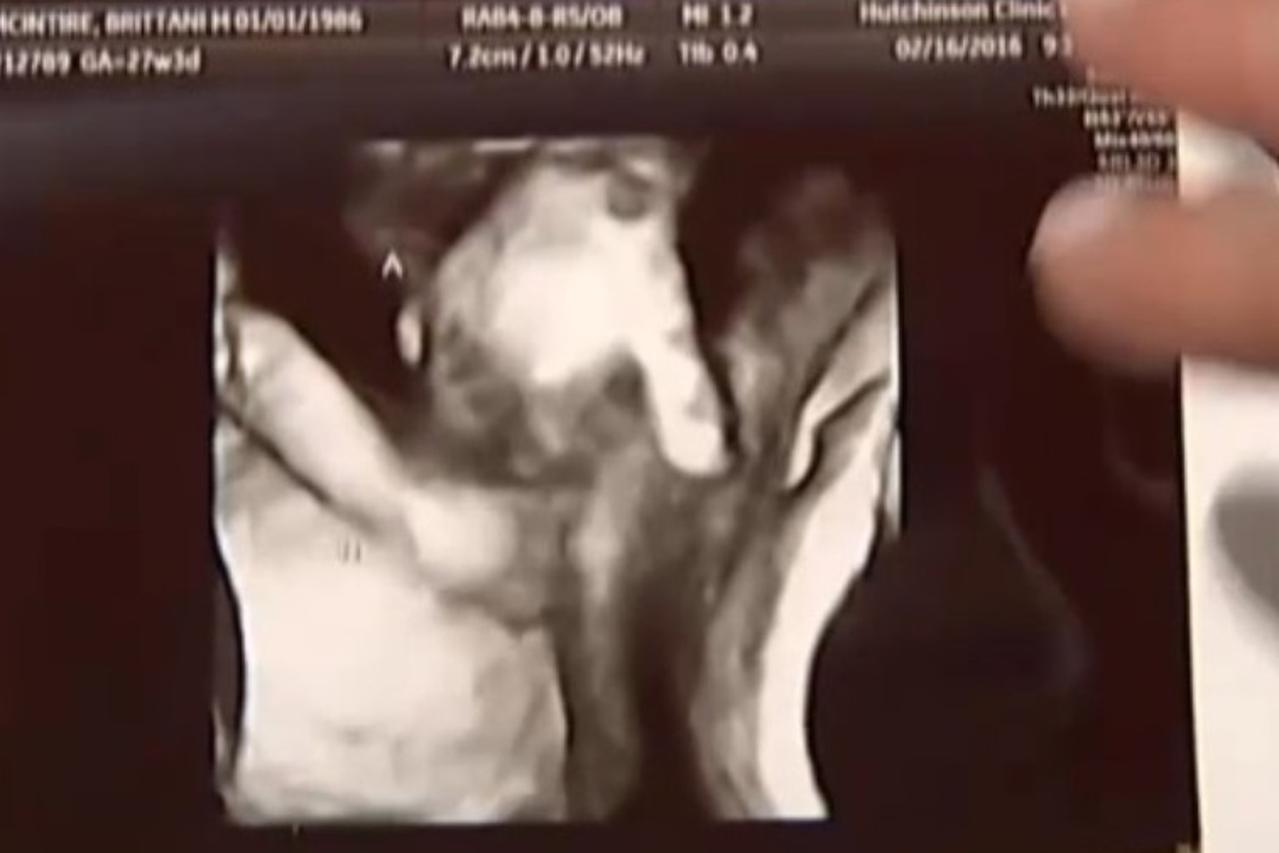

mala utjeha Nakon što je saznala da joj jedno dijete umire, vidjela ovu sliku ultrazvuka Brittani i njezin suprug Ian nisu planirali imati još djece, a kamoli blizance